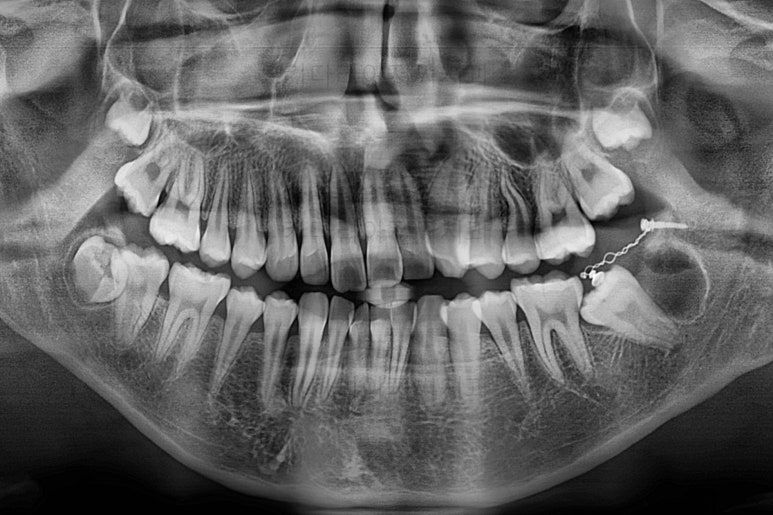

X-ray를 보면 사랑니가 어부바 하고 있어서 나와야 될 어금니가 짓눌려 있는 양상이었어요.

이 경우 방향을 잘못잡아서 바로 앞 어금니도 밀어버리거나 해를 가할 수 있는 상황이었습니다.

사랑니가 잘못 나는 바람에 사랑니 포함 치아 3개가 문제될 수 있는 상황이었어요.